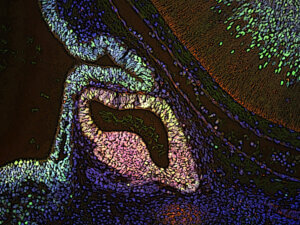

Dr. Aubrey Converse and a Northwestern University team tied for second place with this image of an ovarian follicle from a mouse.

Dr. Anzela Niraula’s grand prize-winning image shows the microglia mandala shows microglia (green) and POMC neurons (grey) within the arcuate nucleus of the hypothalamus in the brain. The regulation of POMC neurons has implications for both obesity and diabetes.